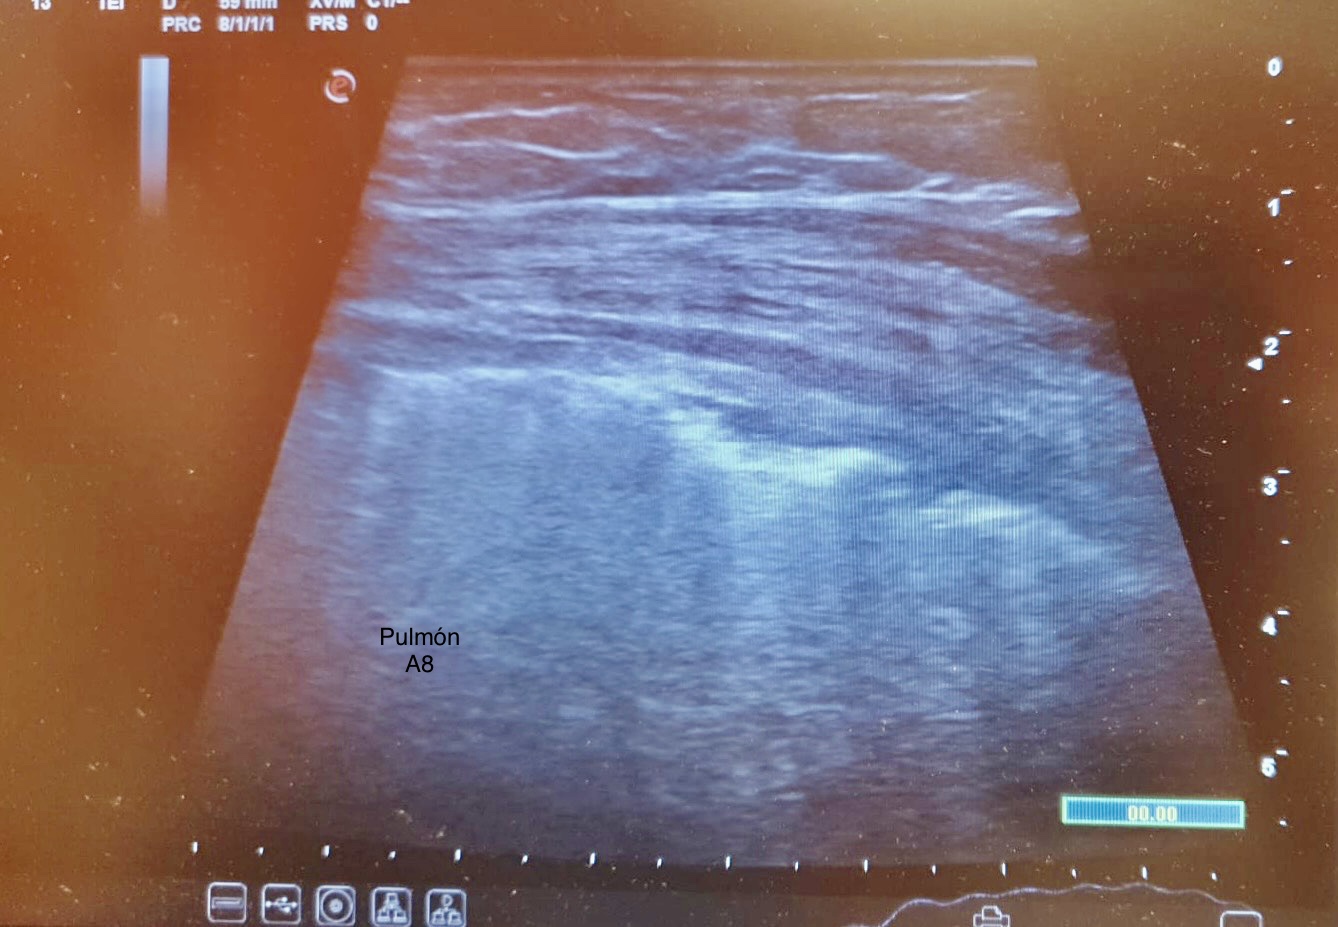

El examen eFast muestra sliding presente con línea pleural irregular y líneas B en la zona del traumatismo. Resto de zonas del examen negativas. La ecografía costal muestra imágen disrupción de la cara anterior de la cortical ósea de la séptima costilla compatible con una fractura costal.

La ecografía muestra una fractura con edema pulmonar focal secundario, sin otras complicaciones.

A las 48 horas el dolor estaba controlado con la medicación y el edema pulmonar se había resuelto.